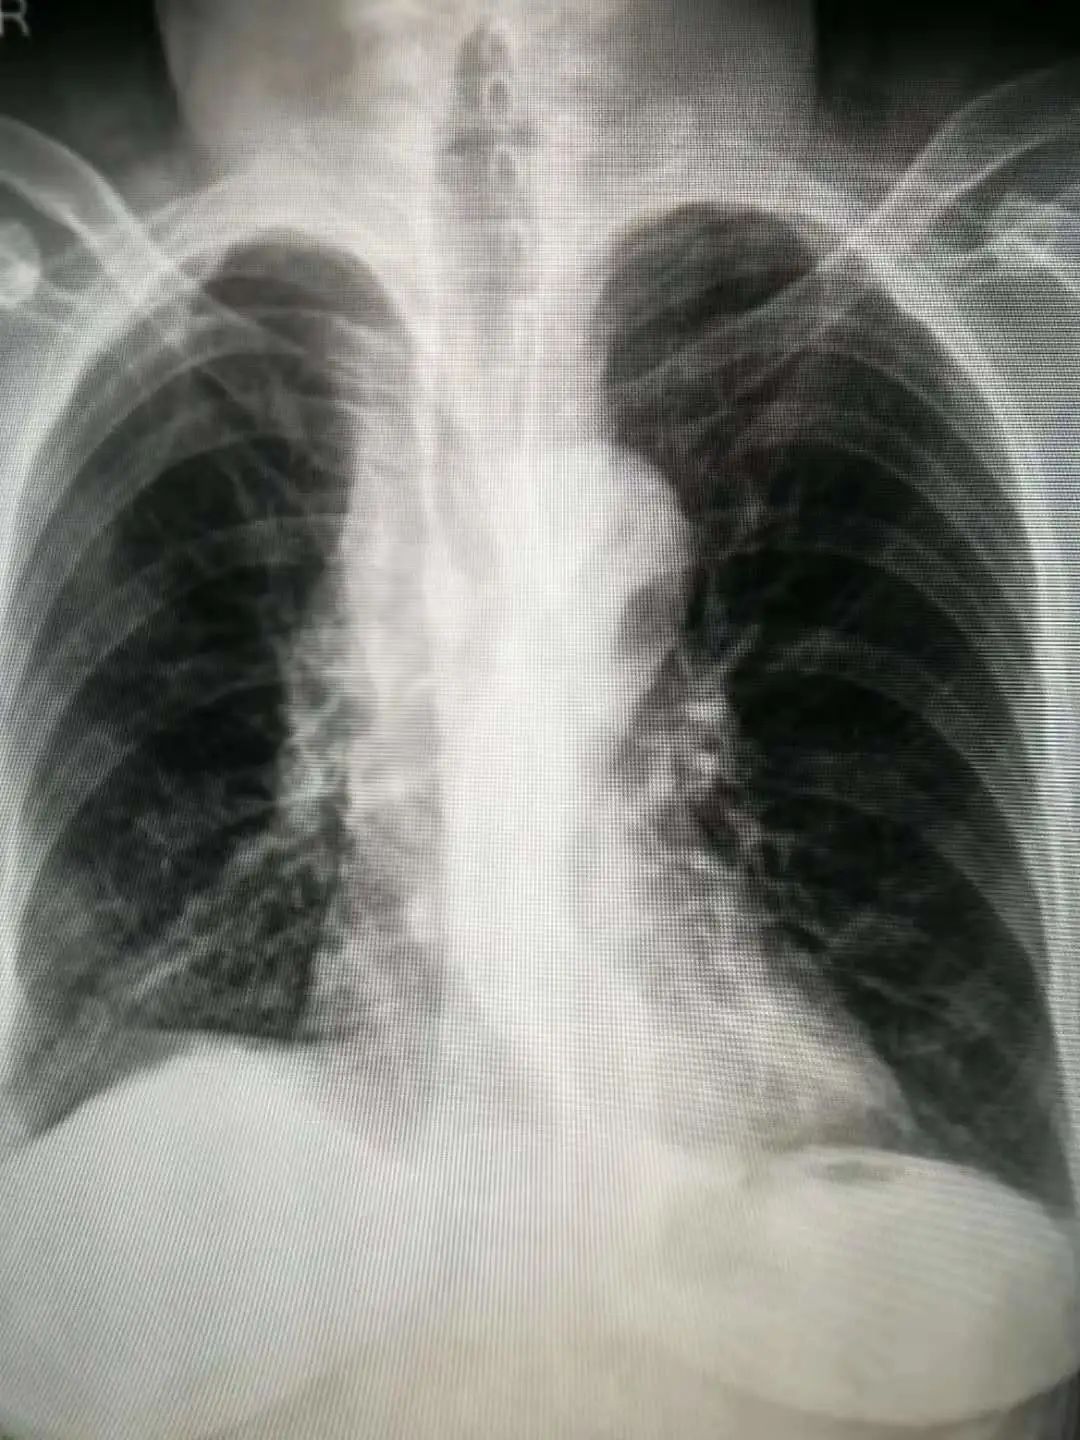

前不久,69岁的李奶奶在体检时发现“右肺上叶占位性病变2周”,家人赶忙为李奶奶办理了住院手续。据李奶奶的主管医师王刚介绍:“老人来院时,胸部CT显示右肺上叶占位性病变,位于后段,大小约2.0×1.8cm,边缘见毛刺及分叶,邻近胸膜略增厚、牵拉,属于发现比较及时的早期肺癌。”